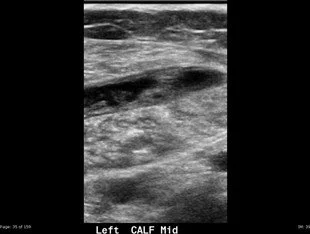

A 62-year-old female presented with two weeks of left calf tenderness and swelling (Figs. 1 and 2). She reported acute medial calf pain that began suddenly while walking and worsened with dorsiflexion.

• Linear collection of fluid and echogenic material separating the superficial gastrocnemius muscle (G in Figs. 3 and 4) from the deeper soleus muscle (S in Figs. 3 and 4).

• Comparison to the normal tendon anatomy (arrows in Figs. 5 and 6) shows significant disruption at the expected location of the plantaris tendon.

• In the event of a complete tear, the plantaris muscle retracts proximally, leaving the torn tendon tract filled with fluid or hematoma. This results in a linear, tubular, heterogeneous fluid collection located between the gastrocnemius muscle anteriorly and the soleus muscle posteriorly.